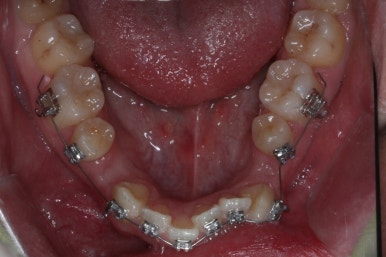

아래 치열은 거의 완료가 되었네요.

이 뽑은 자리도 다 없어졌고요. 대신 윗니는 어금니쪽에 약간의 틈과 기울어진 경사 등등 디테일한 조절을 계속해 나갑니다.

가장 최근의 사진입니다.

아직 치료 종료는 안되었으나 약간의 조절을 더하면 치료를 마무리할 수 있을 것 같습니다.

물론 윗니 한 쪽은 작은 앞니가 없고 한 쪽은 작은 어금니가 없기 때문에 중앙선이 100% 일치하지는 못하겠지만 기능적으로나 미적으로나 매우 개선되었음은 틀림없습니다.